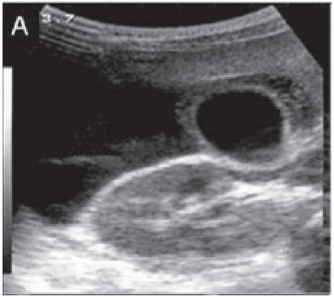

A febre do dengue hemorrágico (FDH) é uma arbovirose responsável por epidemias anuais no Brasil. Sua principal característica é o aumento da permeabilidade capilar, representada pela fuga de líquido e albumina para o espaço extravascular, levando a derrames cavitários e hemoconcentração com elevação do hematócrito, descrita como polisserosite, classificada em formas leves e graves, segundo critérios da Organização Mundial da Saúde. Embora os achados à ultrassonografia sejam inespecíficos, o método contribui para o diagnóstico precoce em pacientes com FHD e no diagnóstico diferencial de outras doenças febris.

Considerando as informações abaixo, assinale a alternativa correta quanto à principal hipótese diagnóstica da imagem ultrassonográfica apresentada.